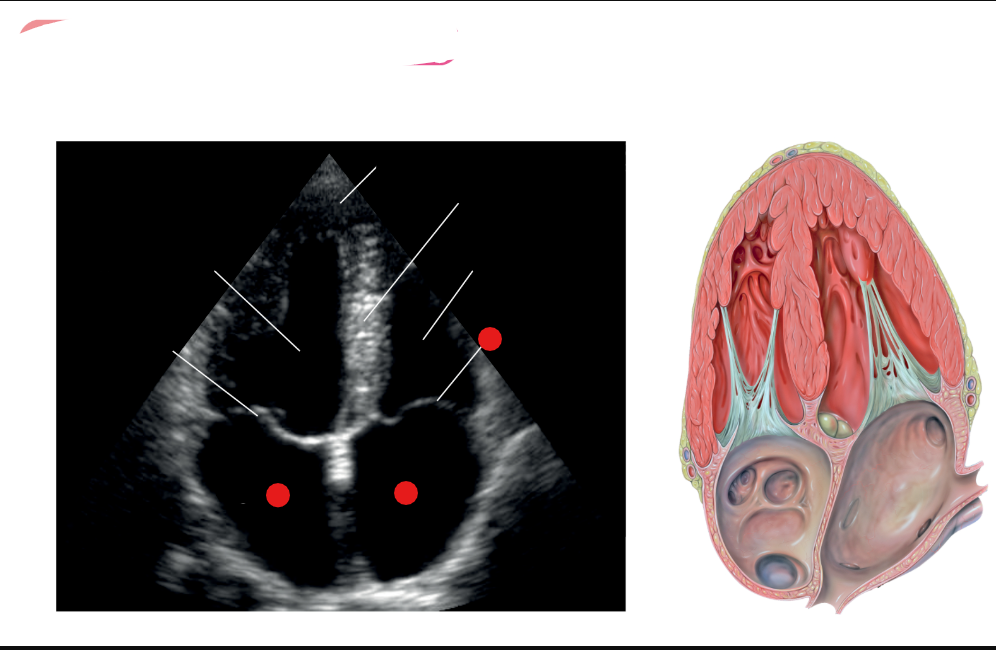

what are the white labels

RV

LA

LV

LVOT

AO

What is this view

parasternal long axis of the heart

What view is this

label red